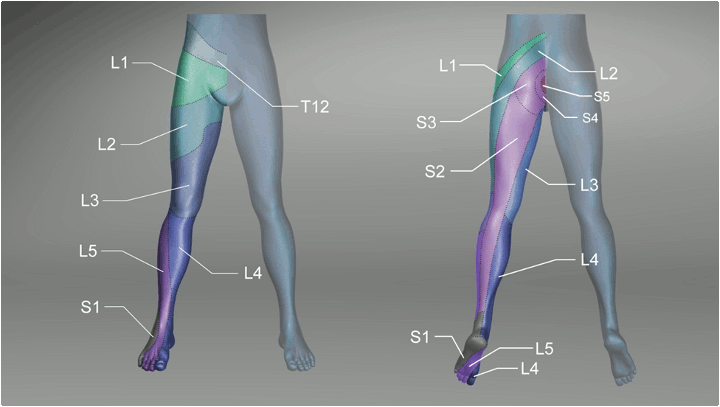

Sensory dermatomes of the lower back and leg